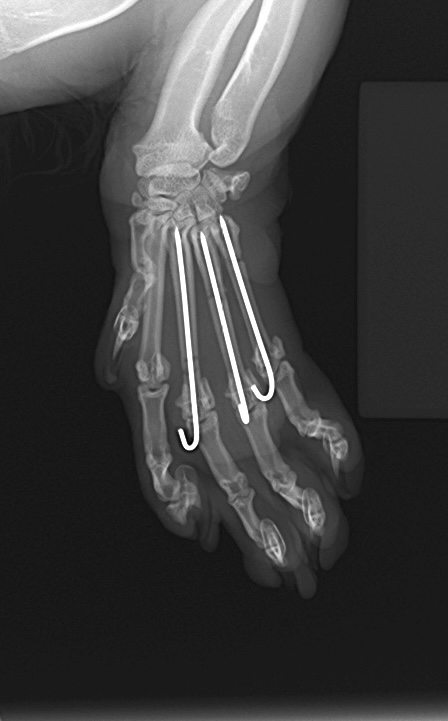

今回はピンニングによる整復を行いました。

術後はギブス固定を行い、骨の癒合を確認後

手術から約2ヶ月後に抜ピンを行いました。